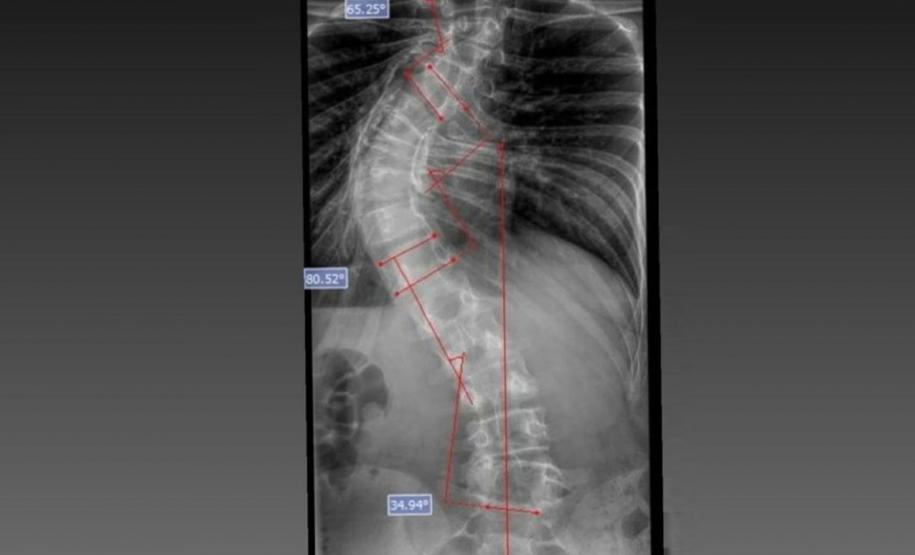

O médico João Elias explica que a escoliose é um termo usado para quando você olha a coluna e percebe uma curvatura. Pode acontecer por várias causas, desde uma escoliose congênita, quando o bebê nasce com uma vértebra mal formada e essa vértebra vai levando ao desenvolvimento de uma deformidade na coluna; a neuromuscular, causadas por doenças neurológicas ou musculares, como uma paralisia cerebral, até as idiopáticas, causadas por alterações genéticas e que podem se desenvolver apenas na adolescência.

Segundo ele, o verão é o período em que mais se diagnostica a doença. Por causa do uso de roupas mais leves, é mais fácil notar a alteração na coluna. Caso seja percebida alguma alteração, uma avaliação ortopédica deve ser marcada. “O diagnóstico precoce é importante. Quando a gente percebe que a coluna está iniciando uma curvatura é possível controlar essa curva. Fazer o procedimento com uma curvatura menor permite melhores resultados na cirurgia”, explicou.